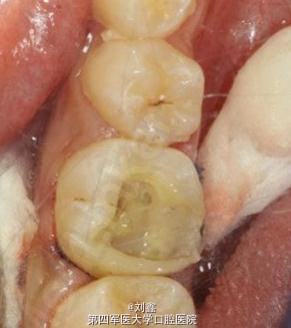

局麻下牙龈息肉切除及开髓去腐,后牙根管治疗后纤维桩+树脂充填

采用纤维桩+树脂充填还是桩冠修复我也纠结过,其实根据影像、牙齿的生长发育和实际情况,我个人认为这样的病例做桩冠修复也是合情合理。但患者的家长考虑小孩子尚小处于生长发育期倾向前者,何况成年后也可直接行冠修复!